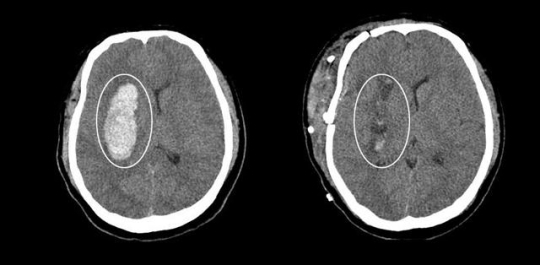

▲ 26세 남자환자의 자발성 대뇌출혈과 개두술 직후 사진.

자발성 뇌출혈의 경우 고혈압과 연관성이 있으며 예전에는 고령에서 주로 발생했지만 최근 식생활등의 변화로 인해 20~30대의 젊은 연령에서도 발생률이 증가하고 있다. 갑작스런 의식소실 또는 반신마비로 응급실에 내원하게 되며 대부분의 환자에서 신속한 수술적 치료가 필요하다. 출혈의 위치와 양에 따라 얼마만큼의 신경학적 장애가 남게 될 지 이미 결정이 되지만 수술로 혈종을 제거하고 출혈하고 있는 혈관을 찾아 지혈하게 되면 장애를 최소화하고 사망에 이르는 것을 방지할 수 있다.